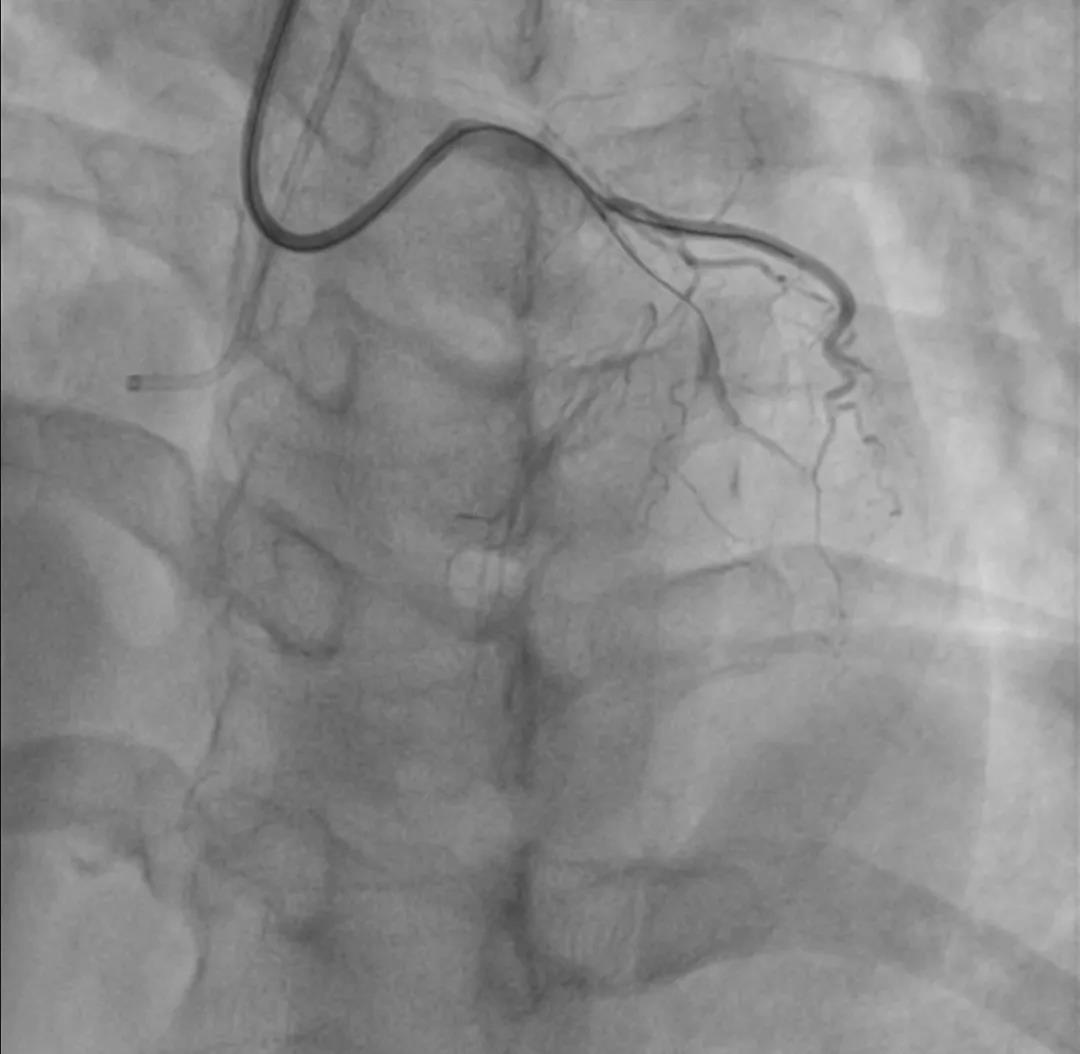

操作过程 XT-R顺利通过第一闭塞段

第二段病变通过困难角度过大更换XT-A仍通过失败 交换双腔微导管+Gaia-2

Gaia-2进入内膜下微调进入真腔交换工作导丝进行IVUS检查

IVUS-1

远段直径2.2*2.4mm

对角支处局限血肿